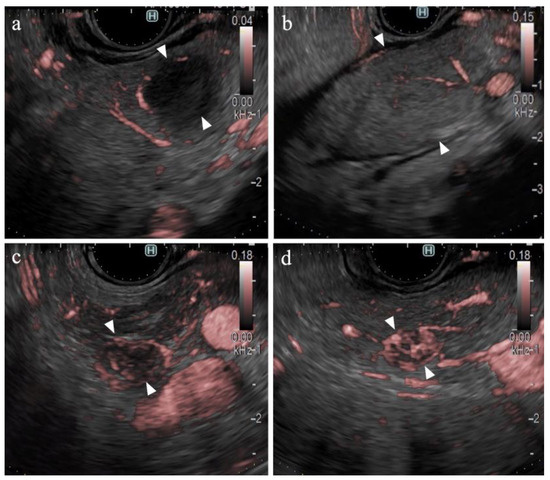

Figure 2.

Diagnostic criteria for DFI. (a) Vascularity was classified as hypovascular or hypervascular. (b) Vessel distribution was classified as peritumoral or intratumoral. (c) Vessel shape was classified as spotted or linear.

The long diameter, depth of the SPLs, and frame rates for eFLOW and DFI were determined from the static images. All B-mode, eFLOW, and DFI images were numbered. Three expert endosonographers, each with over 5 years of experience in EUS and 1 year of experience in DFI-EUS, evaluated the images. Clinical information and final diagnoses were blinded. Figure 1 presents the evaluation criteria. The images were classified as fair or poor regarding evaluability. Echogenicity (hyperechoic, isoechoic, or hypoechoic), border detection (well-defined or indistinct), contour shape (smooth or irregular), and the internal echo of the SPLs (homogeneous or heterogeneous) were classified on B-mode images. The presence of vessels (present or absent), vessel distribution (peritumoral or intratumoral), and vessel form (spotty or linear) in the SPLs was classified on eFLOW images. The presence of vessels (present or absent), vascularity (hypervascular or hypovascular), vessel distribution (peritumoral or intratumoral), and vessel shape (spotted or linear) in the SPLs were classified on the images acquired via DFI (Figure 2). The eFLOW and DFI findings were evaluated only in cases where vessels were present within the SPLs. The “vascularity” on DFI was classified as hypovascular in cases where vessels were not present within the SPLs. When a discrepancy was observed in the findings made by the three readers, the findings selected by the majority of the two were adopted. Diagnostic criteria for pancreatic cancer were formulated based on these findings. The findings of lesions other than pancreatic cancer were also evaluated. Neuroendocrine neoplasm (NEN) and metastasis from renal cell carcinoma (RCC) were collectively classified as “hypervascular tumors” based on historical results [32,33,34].